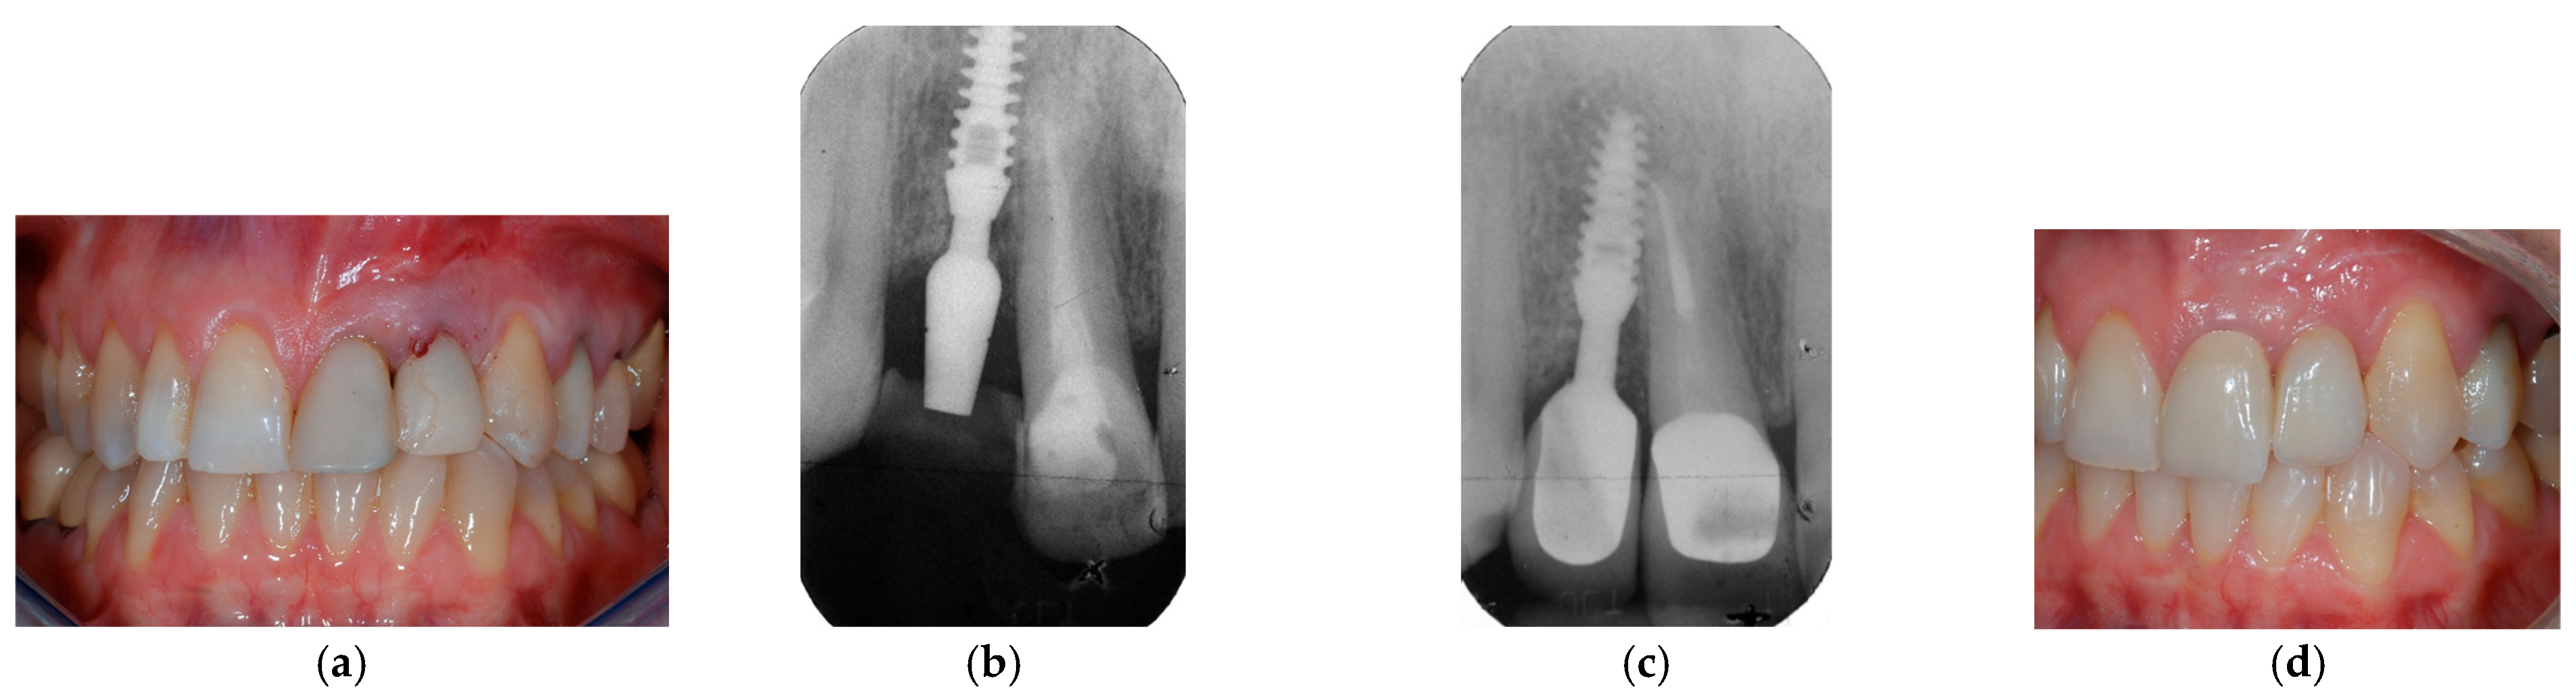

2.9. Clinical Cases and Study Diagram